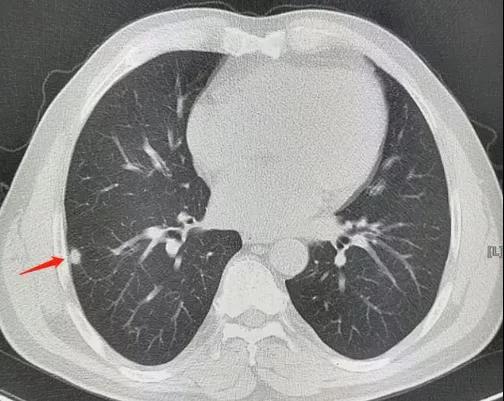

问题三:胸片和胸部ct有什么区别,该如何选择?

答:相比胸片而言,ct的精确性更高,特别是对于早期肺癌的发现上,只有ct才能给出提示。所以,如果是年轻人,需要排除结核感染等可以做胸片,如果是想看的更细,筛查早期肺癌,则需要做胸部ct。

为了提高早期肺癌诊治率,胸部放射检查已纳入常规体检,随着临床病例肿瘤发病愈趋年轻化,省二中医院医生建议,超过35岁的人群体检建议常规做胸部ct,对于青少年如入学、入职体检,可做胸部x线平片。